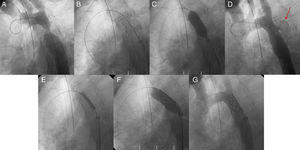

Patient 2 was a woman with a long-standing recoarctation that was treated using a Palmaz stent. The mid-portion of the stent was underexpanded and had to be redilated using a high-pressure Mullins balloon. Aortic rupture occurred with massive thoracic hemorrhage. This led to hypotension, extreme bradycardia, and cardiac arrest; a CS was immediately implanted in the stent and the patient recovered (Fig. 4). Subsequently, the hemothorax was drained and the outcome was favorable.

Figure 4.Patient 2, ruptured aorta. A, aortography showing a large recoarctation; B, underexpansion of the Palmaz stent. C, post-expansion to 9atm using the Mullins balloon; D, aortic rupture and contrast leaking into the chest (arrow); E, covered stent in the stent prior to expansion; F, expansion of the covered stent in the stent; G, completely sealed aortic rupture.